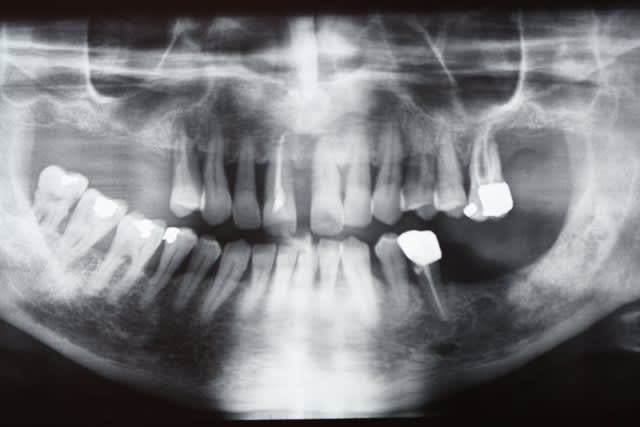

T'as perdu tes cours de paro (rd de gauche) ...)))

Absolument pas perdu les cours de paro

Suivra implanto totale haut et bas

Pour le haut, les incisives bougaient tellement que j ai dû commencer par régler le secteur antérieur de 5 à 5

Ensuite je vais virer les molaires avec PRFs puis ostéotension et poser des implants distaux que je relierai aux implants antérieurs qd ils seront intégrés

Pffft, paro et en plus, il ne sait pas faire une pano...

Photo d une pano argentique sur le négato donc je cadre plus serré pour pas te montrer les condyles inutilement